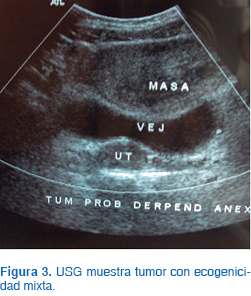

Se realizó USG, encontrándose un tumor con ecogenicidad mixta (Figura 3). La TAC mostró un tumor dependiente de ovario derecho con dimensiones de 6 x 9 x 9 cm de diámetro, con patrón mixto (Figura 4). Se realizó la determinación de alfa fetoproteína, con resultado de 2 μg/L; la fracción β de la gonadotrofina coriónica fue de 1 mUI/mL; la hormona luteinizante (LH), de 6 mUI/mL; la hormona folículo estimulante (FSH) fue de 7.2 mUI/mL; prolactina, 15.9 ng/mL; estradiol, 2.6 pg/mL, y la 17-OH PROG (17-hidroxiprogesterona), de 0.5 ng/dL.